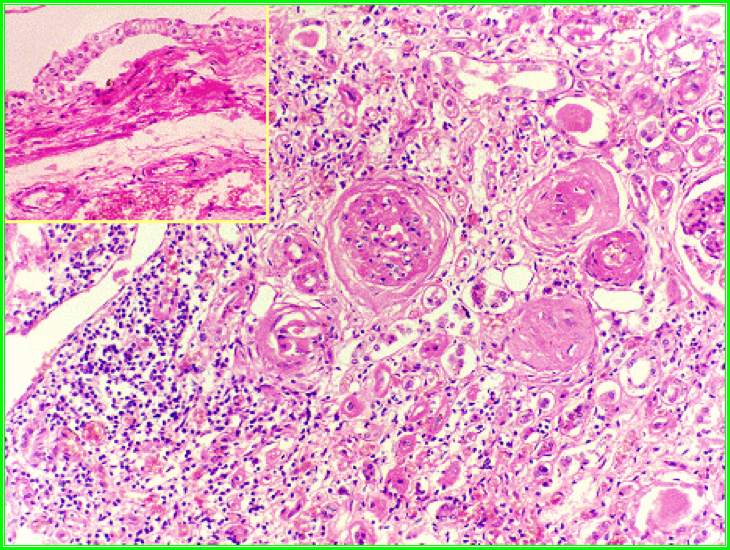

2. 镜下,病变呈不规则灶状分布,肾间质大量淋巴细胞和巨噬细胞浸润,淋巴滤泡形成,间质纤维化。部分肾小管萎缩,基底膜增厚,进而肾小管坏死、消失。部分肾单位代偿性肥大,肾小管扩张,管腔内充满红染的胶样管型,形似甲状腺滤泡,称为甲状腺样变(thyroid like appearance)。活动期可见中性白细胞浸润及脓肿。早期,肾小球病变较轻,仅可见肾小球周围纤维化 (periglomerular fibrosis)。末期,包括肾小球在内的肾单位整体荒废,肾小球发生萎缩、纤维化、玻璃样变。动脉内膜高度增厚,管腔狭窄。